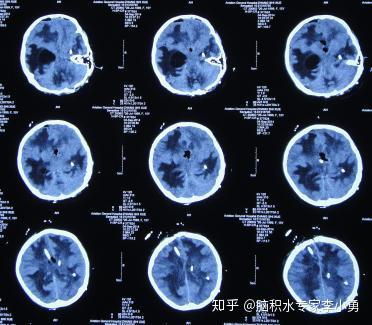

小脑蚓部髓母细胞瘤术后脑积水 4次脑室外引流术和腰大池引流术后颅内感染仍加重致脑室粘连 知乎